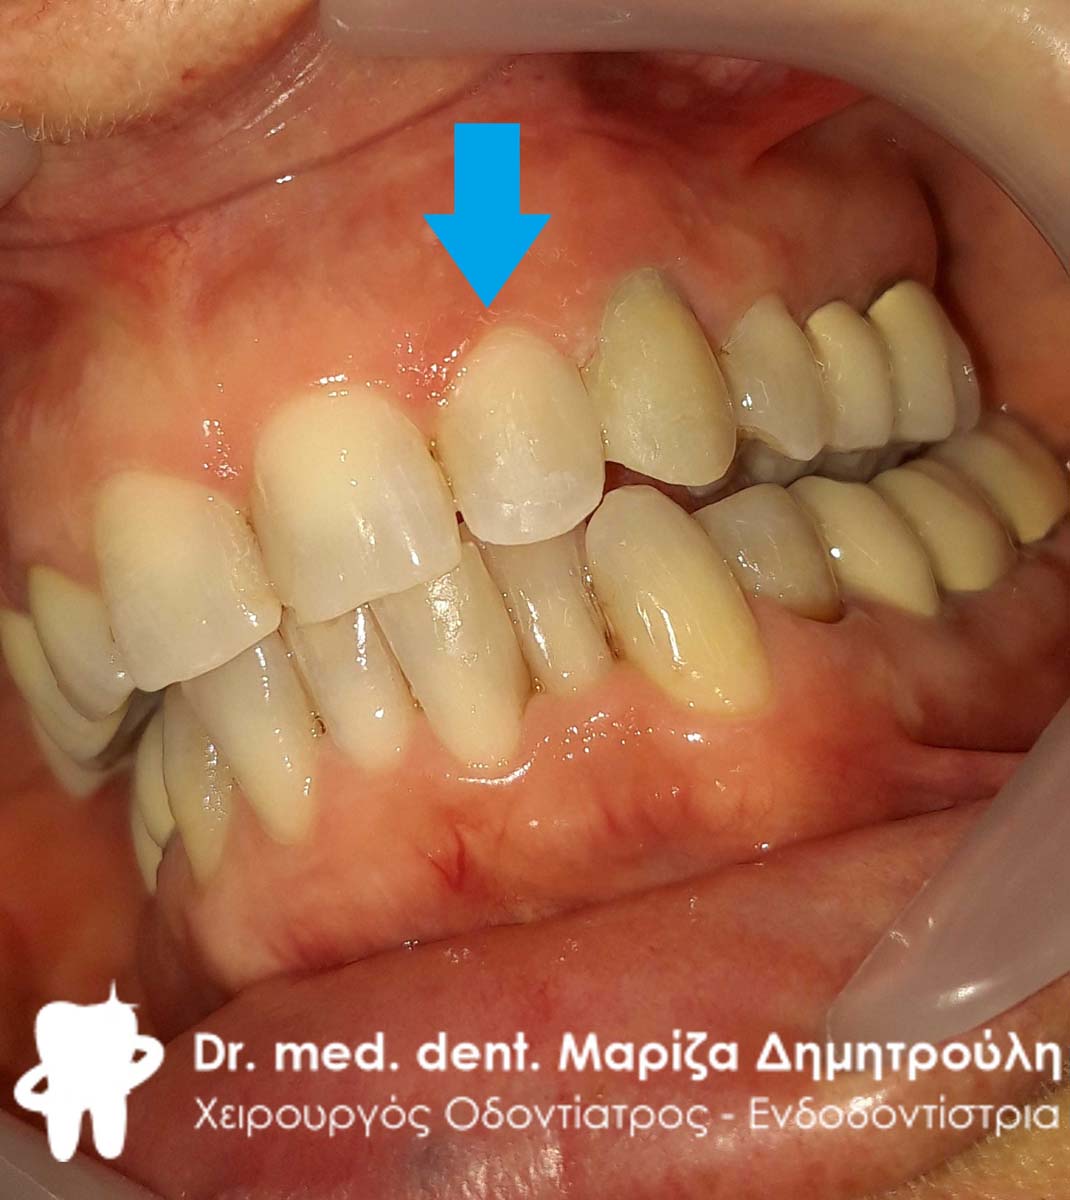

Ο ασθενής επισκέφτηκε το ιατρείο με σκοπό την αλλαγή ενός παλιού λευκού σφραγίσματος που υπήρχε στον αριστερό κυνόδοντα της άνω γνάθου. Το συγκεκριμένο δόντι τον ενοχλούσε τόσο αισθητικά, καθώς παρουσίαζε δυσχρωμίες όσο και λειτουργικά, γιατί πολλές φορές τον ενοχλούσε κατά τη μάσηση.

Μετά την κλινική εξέταση διαπιστώθηκε οτι το συγκεκριμένο δόντι είχε επανατερηδονιστεί. Η θεραπεία επιλογής ήταν η αφαίρεση του παλιού δυχρωμικού παλιού λευκού σφραγίσματος και η αντικατάσταση του με νέο λευκό σφράγισμα ρητίνης.

ΠΡΙΝ

META